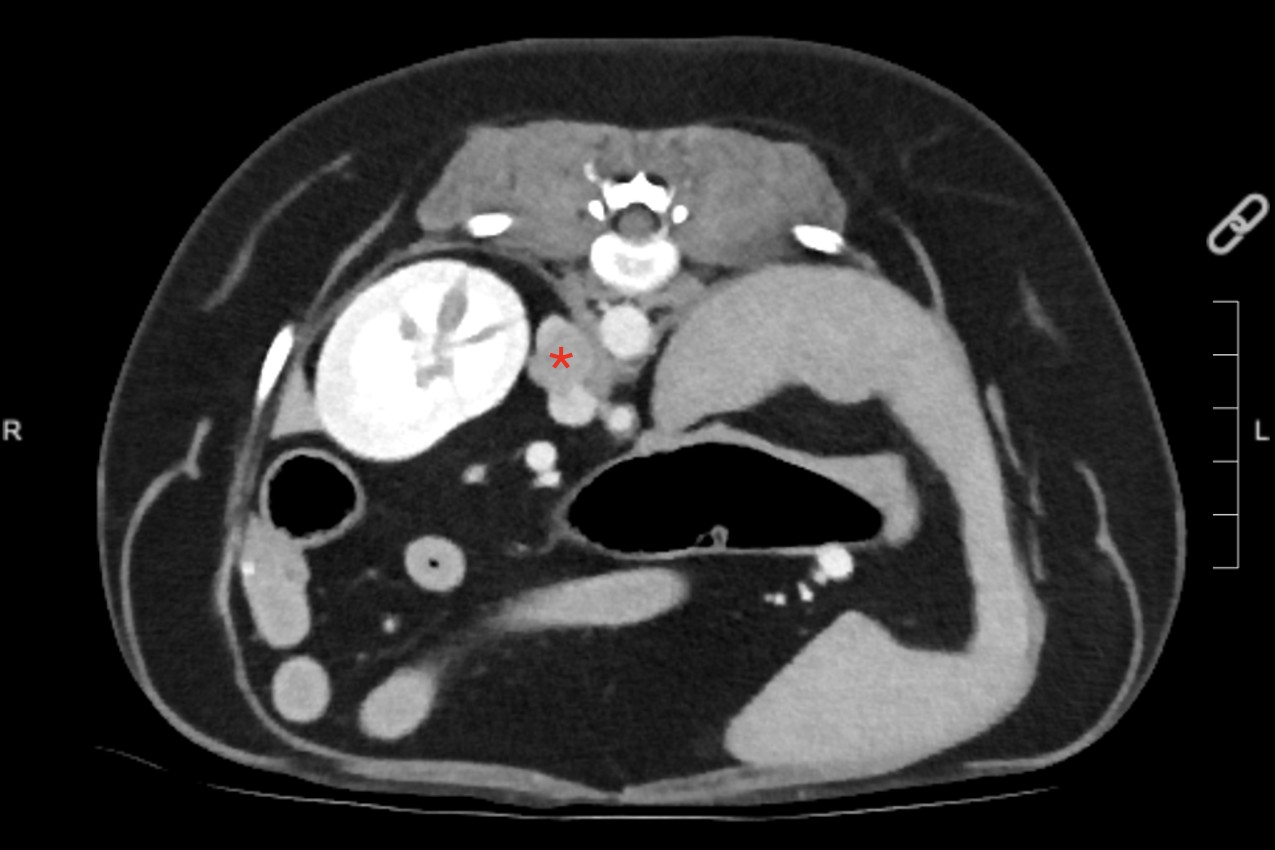

Pheochromocytoma is a tumour that occurs in both dogs and humans, and develops in the adrenal medulla, the innermost part of one or both adrenal glands. It is characterised by the overproduction of hormones, such as ephinephrine and norephinephrine, which triggers the “fight or flight” response and can be life-threatening due to the cardiac complications it causes. Canine and human phaeochromocytoma share many clinical and biological features, and investigation of phaeochromocytoma from pet dogs is also important because it can be used as a research model for human phaeochromocytoma.